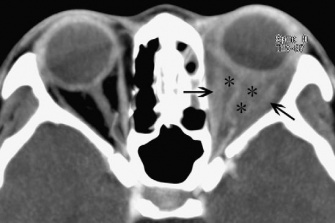

Enlargement of the extraocular muscles will be seen (single or multiple). Unilateral single muscle inflammation with tendon involvement is most common. The most frequently involved muscle is the medial rectus followed by the superior rectus, lateral rectus and inferior rectus. The tendon often also enlarges with the muscle belly, unlike in thyroid orbitopathy in which the tendon is classically "spared" (Figure 3). There may be infiltrates throughout the orbital fat bordering the muscle, blurring the margin of the muscle.

Figure 3: CT image of bilateral medial and lateral rectus tubular-like enlargement with tendon involvement. (Courtesy of Z.X. Ding)